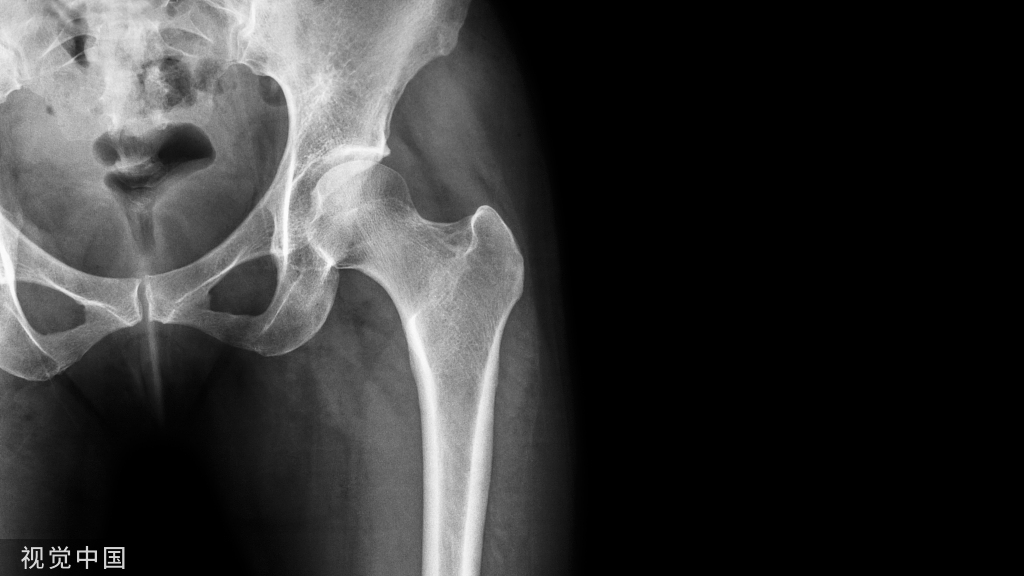

CT显示一个粗隆间骨折